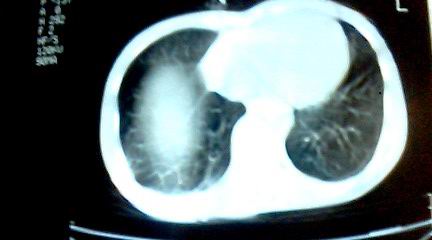

标题: CT25218:请教!胸部CT,胸8椎体骨质破坏,伴周围软组织肿。 [打印本页]

标题: CT25218:请教!胸部CT,胸8椎体骨质破坏,伴周围软组织肿。

患者,女41岁,肢体乏力。

双肺及胸椎结核。

两肺上叶继发性肺结核;胸椎结核并椎旁寒性脓肿形成。

支持,不过本人还要说有的占位和其它炎症也这样,你要是看到1000个这样的都报结核了,我保你其中必有错的

恶性,椎体淋巴瘤或pnet并肺内转移。